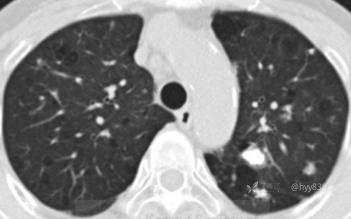

简要病史:59y/F,咳嗽伴胸部不适半年,既往史:肛门癌、SLE(系统性红斑狼疮)、狼疮性肾炎

胸部平片